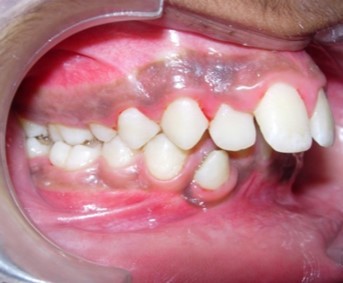

Intraoral assessment. (Figure 1d,Figure 1e,Figure 1f,Figure 1g,Figure 1h).

Figure 1e.Pre-treatment intra-oral-Right

Pre-treatment intra-oral-Right

The maxillary arch was V-shaped with severely proclined and rotated maxillary incisors with a palatally placed 12. The mandibular arch was U-shaped with severe crowding of mandibular incisors, with 43 partially erupted and buccally placed with transpositioned 42 and 43, with 42 mesiolingually rotated, 33 distolingually rotated and 34 distolingually rotated and buccally placed.

Severe increase in overjet and deep bite were both observed. The maxillary midline coincided with the skeletal midline but the mandibular midline was shifted to the right side by 1 mm. Bilateral maxillary posterior crossbite was also observed. On right side the molar relation was Class I and on the left side it was Class II. The canine relation was Class II on the left side and the curve of Spee was increased.